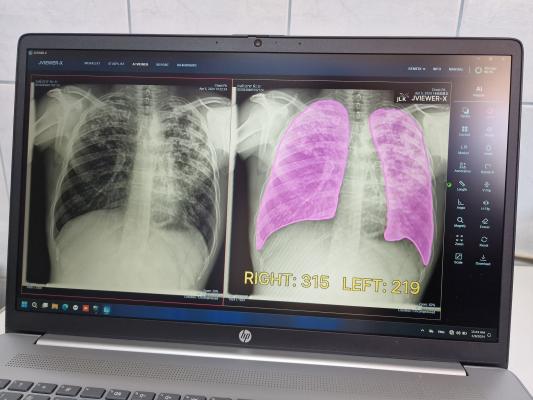

Штучний інтелект проводить автоматичний аналіз, читаючи рентген-знімки, і відображає зони потенційної патології у вигляді теплової карти легень. Це дозволяє виявити ураження з ймовірністю від 1% до 100%.